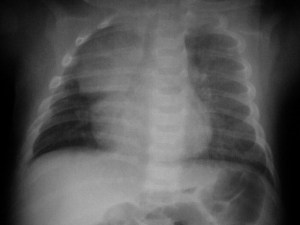

Cuando existe una aparente elevación del hemidiafragma izquierdo pero la burbuja gástrica permanece en su sitio, con el consiguiente aumento de distancia entre la burbuja gástrica y el aparente diafragma, hay que sospechar derrame subpulmonar y no elevación real del hemidiafragma. La fotografía muestra el signo; la flecha negra señala la burbuja gástrica; las flechas rojas marcan el aparente diafragma.

La imagen localizada permite ver mejor, además, el pinzamiento del seno costofrénico izquierdo por el derrame (flecha).